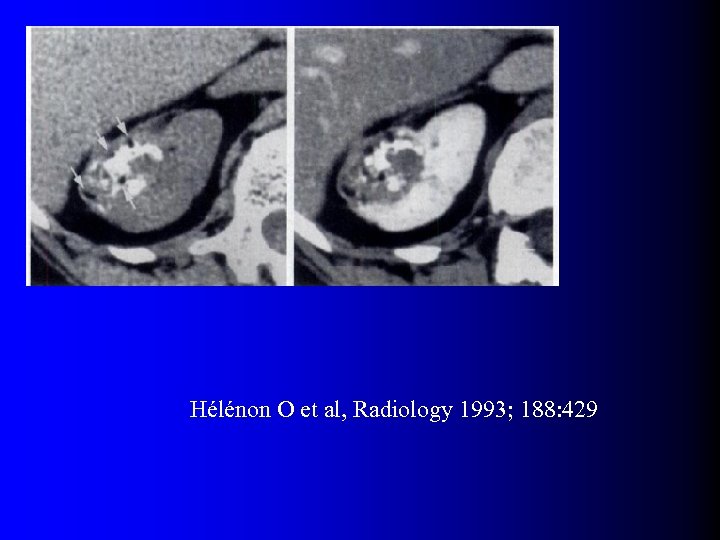

Tumeurs malignes à contenu graisseux l OUI… presque l Quelques rares exceptions dans la littérature – Incorporation de graisse péri-rénale ou sinusale dans une volumineuse tumeur – Métaplasie osseuse avec éléments graisseux de moelle osseuse – Nécrose cholestérolique intra-tumorale (1) Hélénon O et al, Radiographics 1997; 17: 129 (2) Henderson RJ et al, J Urol 1997; 157: 1347 (3) Roy C et al, Br J Urol 1998; 71: 977 (4) Schuster TG et al, AJR 2004; 183: 1402

Tumeurs malignes à contenu graisseux l OUI… presque l Quelques rares exceptions dans la littérature – Incorporation de graisse péri-rénale ou sinusale dans une volumineuse tumeur – Métaplasie osseuse avec éléments graisseux de moelle osseuse – Nécrose cholestérolique intra-tumorale (1) Hélénon O et al, Radiographics 1997; 17: 129 (2) Henderson RJ et al, J Urol 1997; 157: 1347 (3) Roy C et al, Br J Urol 1998; 71: 977 (4) Schuster TG et al, AJR 2004; 183: 1402

Tumeurs malignes à contenu graisseux l Eléments diagnostiques: – Calcifications +++ – Large nécrose intra-tumorale avec petits foyers graisseux – Association avec ADP et thrombus tumoral non graisseux l D'une manière générale, se méfier d'un "AML" à croissance rapide…

Tumeurs malignes à contenu graisseux l Eléments diagnostiques: – Calcifications +++ – Large nécrose intra-tumorale avec petits foyers graisseux – Association avec ADP et thrombus tumoral non graisseux l D'une manière générale, se méfier d'un "AML" à croissance rapide…

Hélénon O et al, Radiology 1993; 188: 429

Hélénon O et al, Radiology 1993; 188: 429